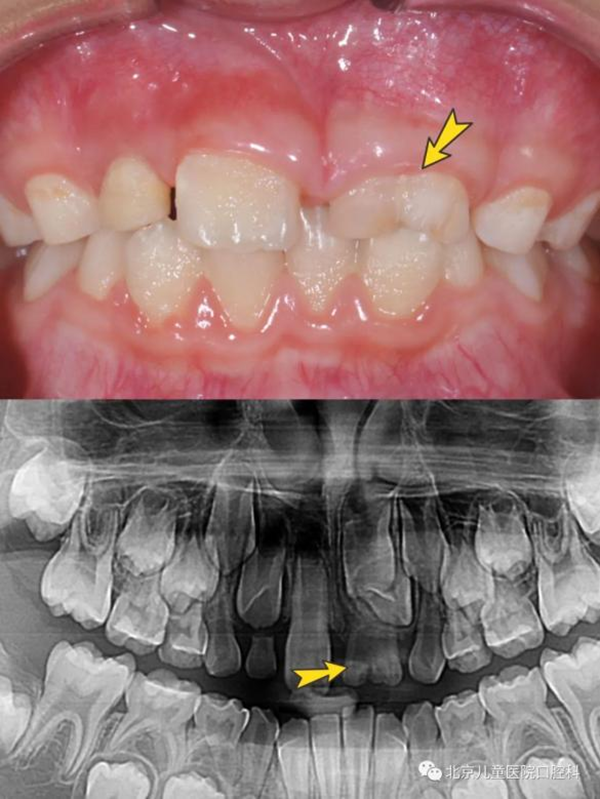

同时,在这个阶段孩子的乳牙逐渐替换为恒牙,有的时候周围的牙都替换了,却只有一颗牙迟迟不松动;有的时候乳牙脱落了很久,新牙还没有长出来;或者新牙长出来却是“扭着身子”的……这有可能是存在多生牙、融合牙、牙齿异位萌出、牙扭转等问题。

这些“隐性”问题可能无法自行发现,建议孩子6至7岁到口腔科就诊进行系统的口腔检查,需要时及时治疗,以免造成更严重的影响。

乳牙是融合牙(上图),对应恒牙牙胚发育异常(下图)

上颌六龄齿卡在前面乳磨牙颈部,位置低,长不出来(上图),六龄齿位置较为隐蔽,萌出时不替换乳牙,萌出障碍很难发现(下图)